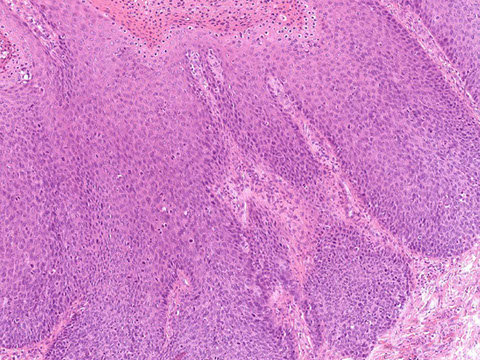

Anal Squamous Cell carcinoma (ASC)